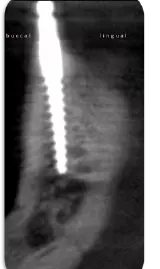

Beim Unterkiefer ist es gut zu wissen, dass man bei einem unbezahnten Patienten durchaus durch den Mentalis-Loop bohren, Knochen-Kavitäten aufbereiten und implantieren kann, da dieser nur die vorderen Frontzähne innerviert. Diese Tatsache erleichtert so Manchem die Planung und Befürchtungen. Bleiben Sie bitte nur ca. 2 mm mesial der beiden Foramina und führen ggfs. auch radiologische Kleinröntgenbild-Messaufnahmen, z. B. mit Condensern, durch.

Ein „Anfänger-Fehler“ ist das zu weite bukkale Aufbereiten der Kavitäten! Deshalb fangen „Routinierte“ immer von lingual kommend mit der Präparation an, richten während des langsamen Bohrens die Bohrer – CNIP-navigiert – auf. Dadurch werden Perforationen ausgeschlossen, die bukkale Wand („Die heilige Wand der Chirurgen“) bleibt vollumfänglich erhalten.